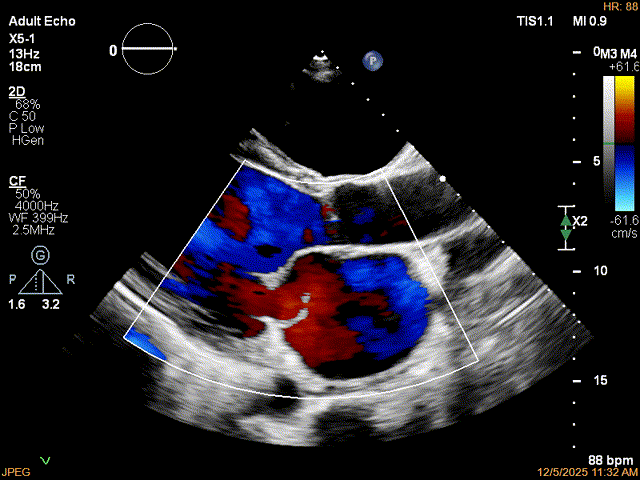

患者食道胃底静脉曲张,遂行TTE术前评估

术前TTE评估:

MR反流病因:DMR(部分腱索断裂)、Carpentier II型;

反流程度:极重度(5+),PISA法估测EROA约1.12cm²,R-VOL约98ml;

病变情况:P2-部分P3,脱垂宽度约27mm ,连枷间距11-13mm,瓣口面积7.8cm²,PML约25mm

其他:TR(重度) ,间接估测PASP约65mmHg;

预估手术难点:后叶冗长,脱垂宽度大,连枷间距大。